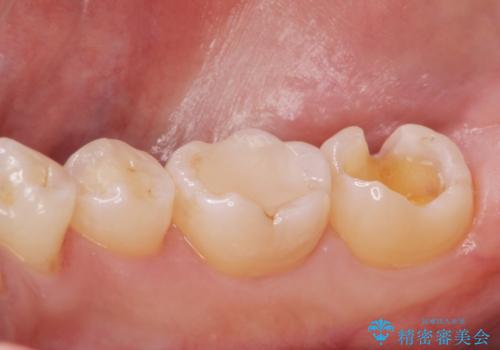

古い樹脂の劣化 セラミックインレー治療

- 保険診療での古い樹脂の劣化が気になるとの事で来院。

二つ樹脂の劣化が見られるので提案をしたが、まずは一つ治療を行いたいとの事でしたので拡大鏡下で劣化した樹脂と虫歯を取り除いた後e-maxインレーにて治療を行いました。

適合の良い詰め物が入りました。

もう一つの治療も現在検討中です。